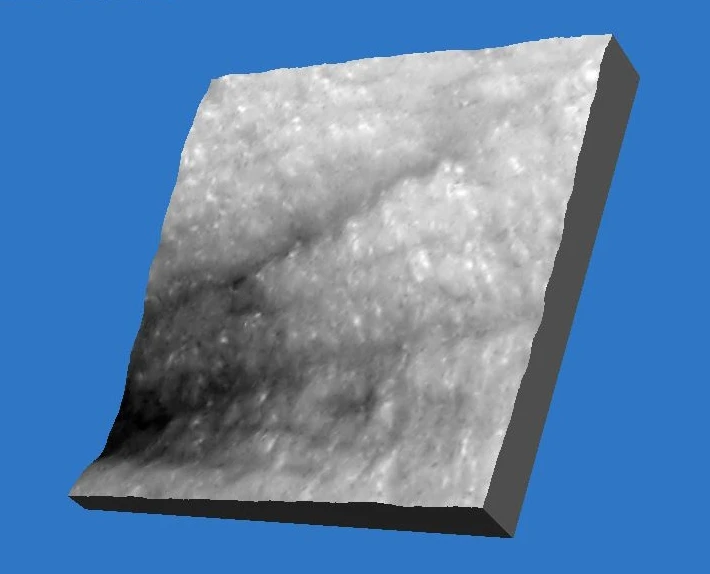

Уже после первой процедуры отмечается выравнивание цвета лица и увеличение тургора кожи (рис. 1-2). Процедуры переносятся очень комфортно, небольшая гиперемия в некоторых случаях держится до 30 минут. По результатам 3D-сканирования уменьшилась выраженность мелких морщин вокруг глаз уже через 6 дней после первой процедуры (рис. 1-6). Также проведено гистологическое исследование сразу после процедуры (рис. 7) (фрагмент «тонкой» кожи: единичными лейкоцитами в толще эпидермиса и на его поверхности, ядра клеток эпидермиса и их цитоплазма на данном участке набухшие, сосочки дермы несколько сглажены, рыхлая волокнистая соединительная ткань сосочкового слоя дермы отечна), на третий день (рис. 8) (отмечается уменьшение количества набухших ядер в эпидермисе, мелкоочаговое кровоизлияние в сетчатом слое дермы с перифокальной сосудистой реакцией и слабовыраженным отеком сетчатого слоя дермы) и спустя 20 дней после процедуры (рис. 9) (В представленном фрагменте кожи заметна умеренная пролиферация клеток эпидермиса и дермы. Отмечается уплотнение коллагеновых волокон сетчатой дермы. Патологических изменений в эпидермисе, дерме, придатках кожи не обнаружено). Также наблюдаются изменения показателей влажности, пигментации и эластичности кожи (рис. 10-11).

Результаты процедуры HELEO4

Рис. 10.